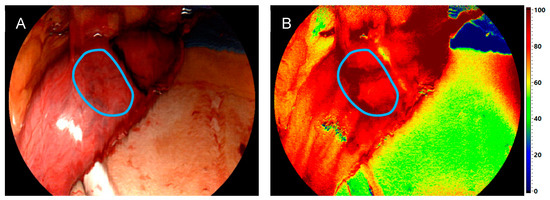

3.2. Comparison of Intraoperative Perfusion Imaging of the Gastroesophageal Sites (Group 1)

3.3. Perfusion Evaluation of the Gastric Conduit by HSI-MIS (Group 1) and HSI-Open (Group 2)

- Thomaßen, M.T.; Köhler, H.; Pfahl, A.; Stelzner, S.; Mehdorn, M.; Thieme, R.; Jansen-Winkeln, B.; Gockel, I.; Chalopin, C.; Moulla, Y. In vivo evaluation of a hyperspectral imaging system for minimally invasive surgery (HSI-MIS). Surg. Endosc. 2023, 37, 3691–3700. [Google Scholar] [CrossRef] [PubMed]